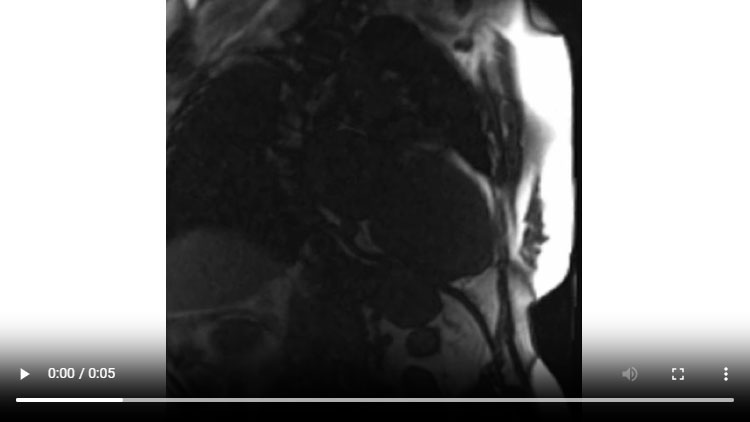

Figure 1C : Séquence Ciné-IRM - Coupes petit-axe apical

- Présence d’une hypertrophie ventriculaire gauche (HVG) asymétrique à prédominance septale mesurée au maximum à 23 mm.

- Visualisation de la sonde de PM avec artéfacts métalliques modérés au niveau du ventricule droit (flèches roses).

- Présence d’un épanchement péricardique de moyenne abondance (flèches rouges).